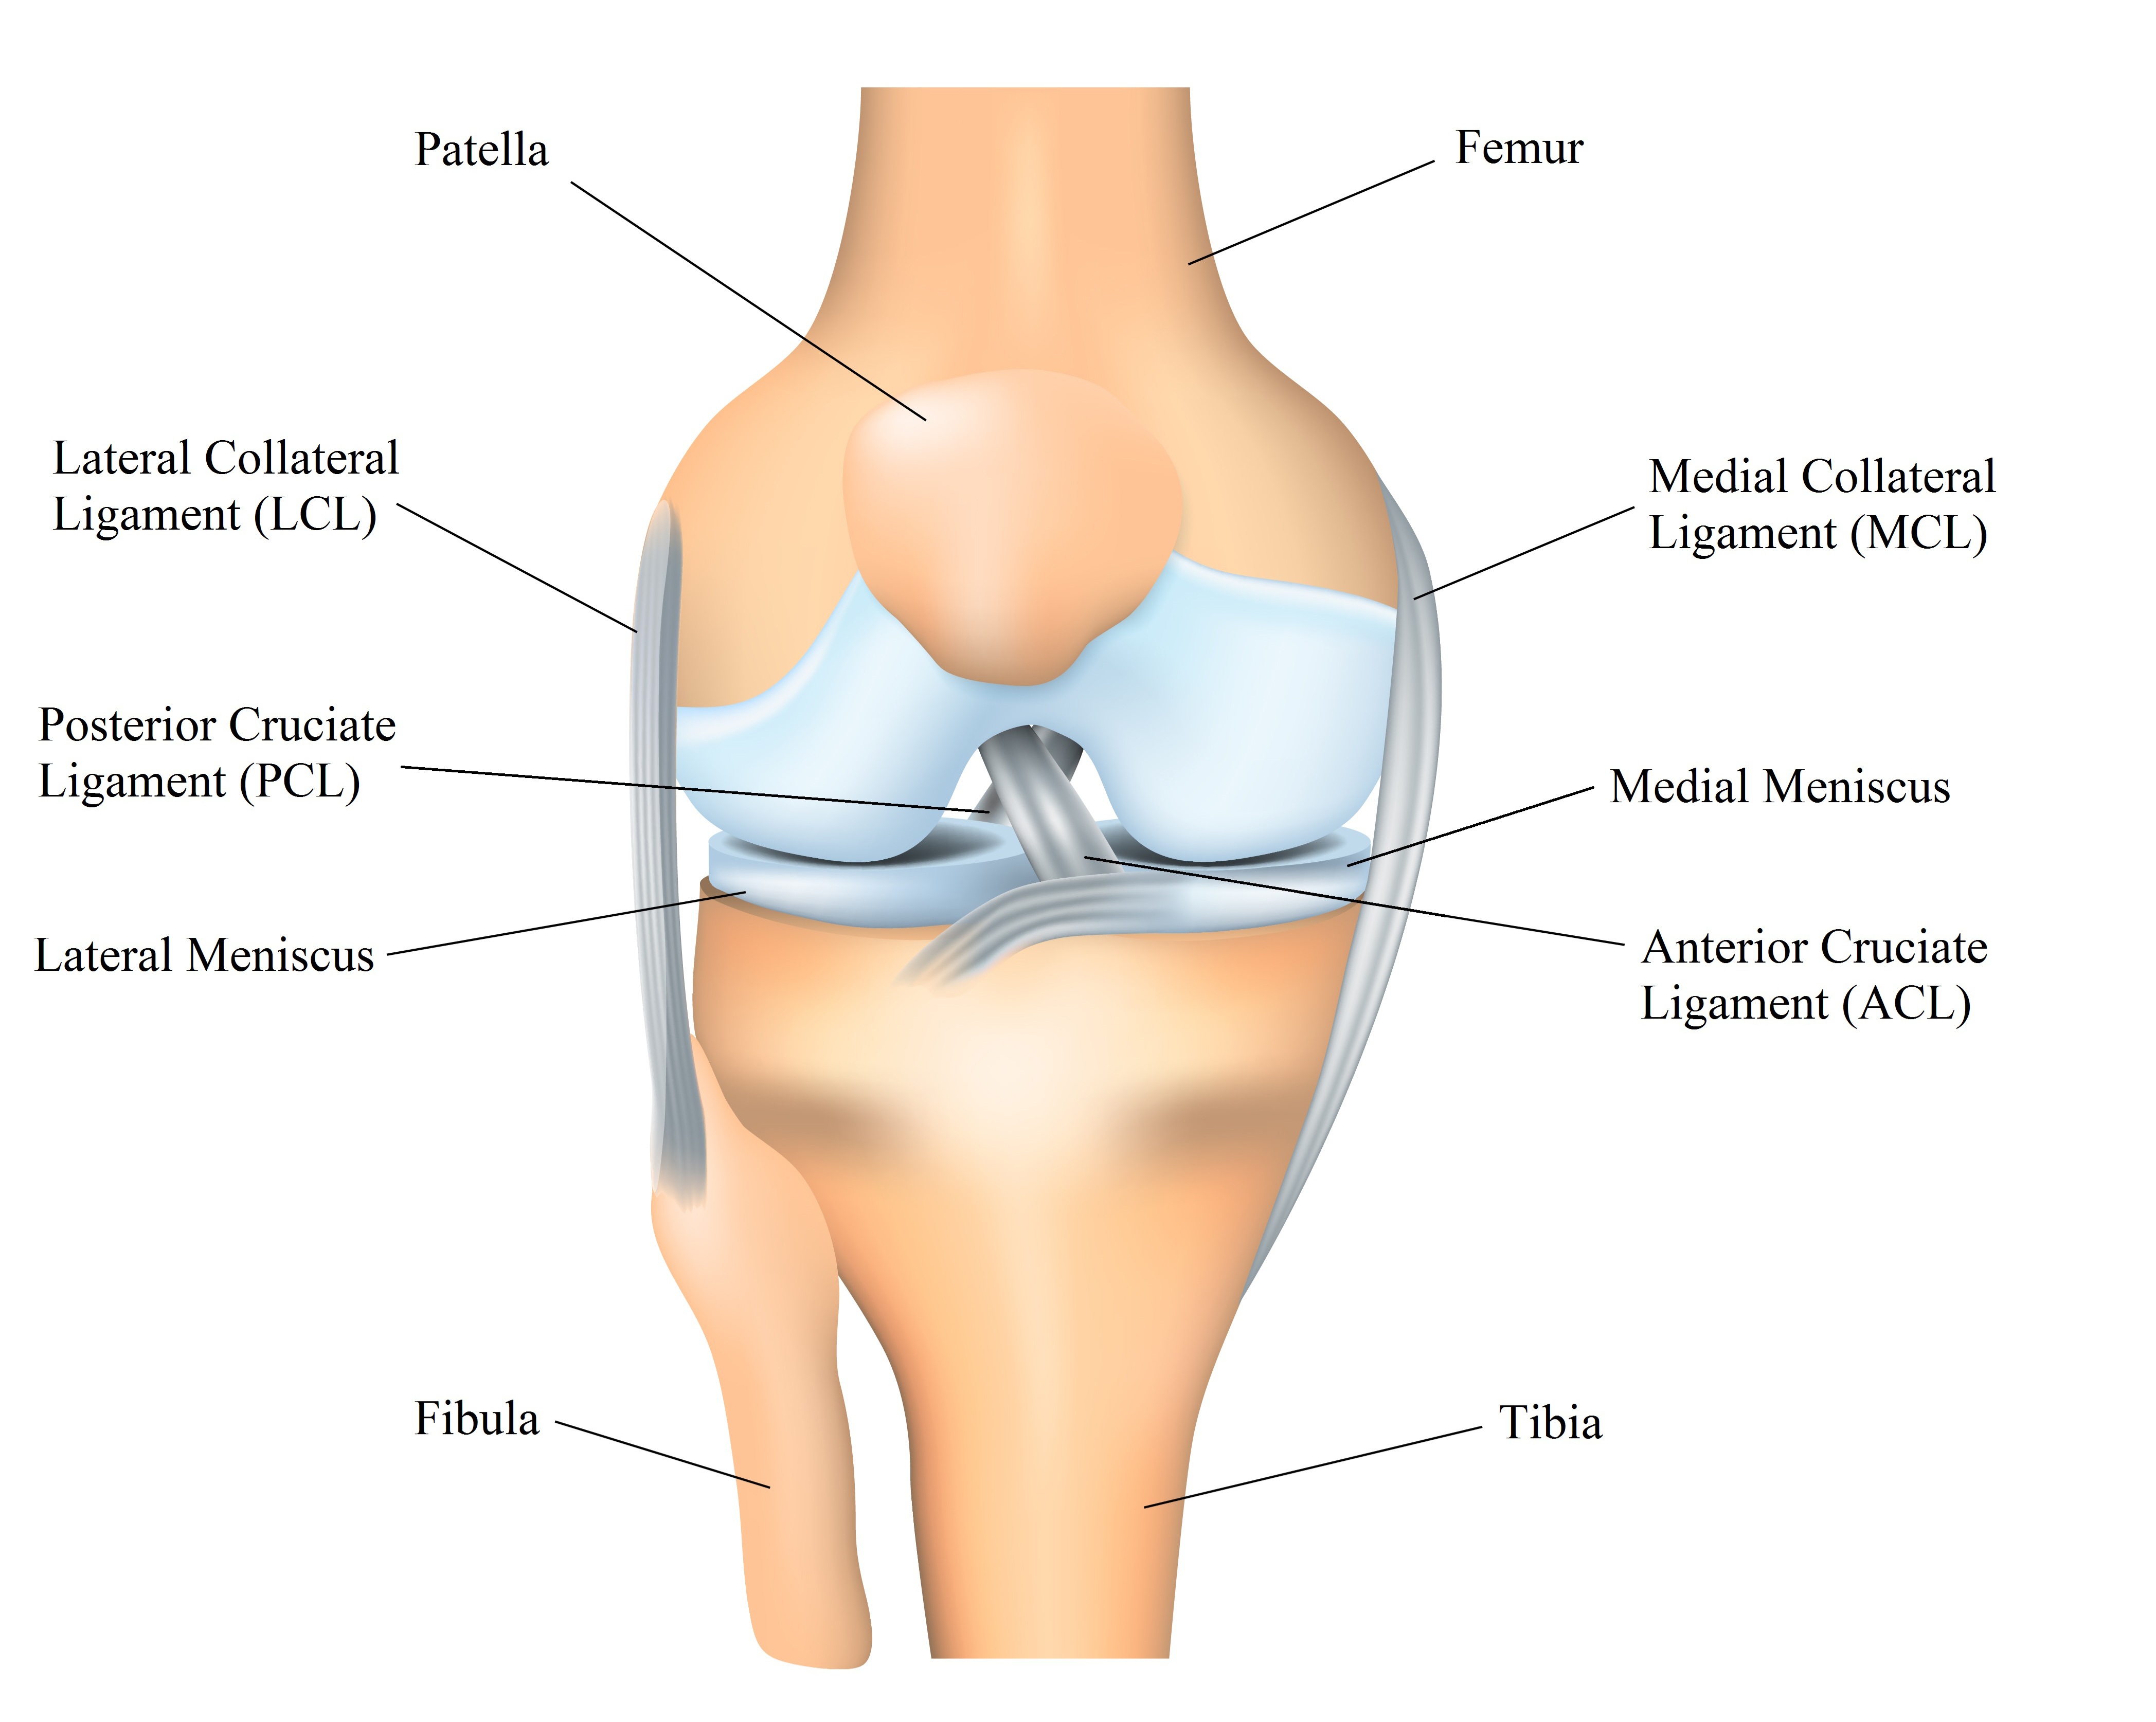

▎آناتومی زانو

زانو یک مفصل پیچیده است که از سه استخوان اصلی تشکیل شده است: استخوان ران (فمور)، استخوان درشت نی (تیبیا) و استخوان کوچک نی (فیبولا).

میان این استخوانها، غضروف مفصلی و مایع سینوویال وجود دارد که به روانسازی حرکات زانو و کاهش اصطکاک کمک میکند.